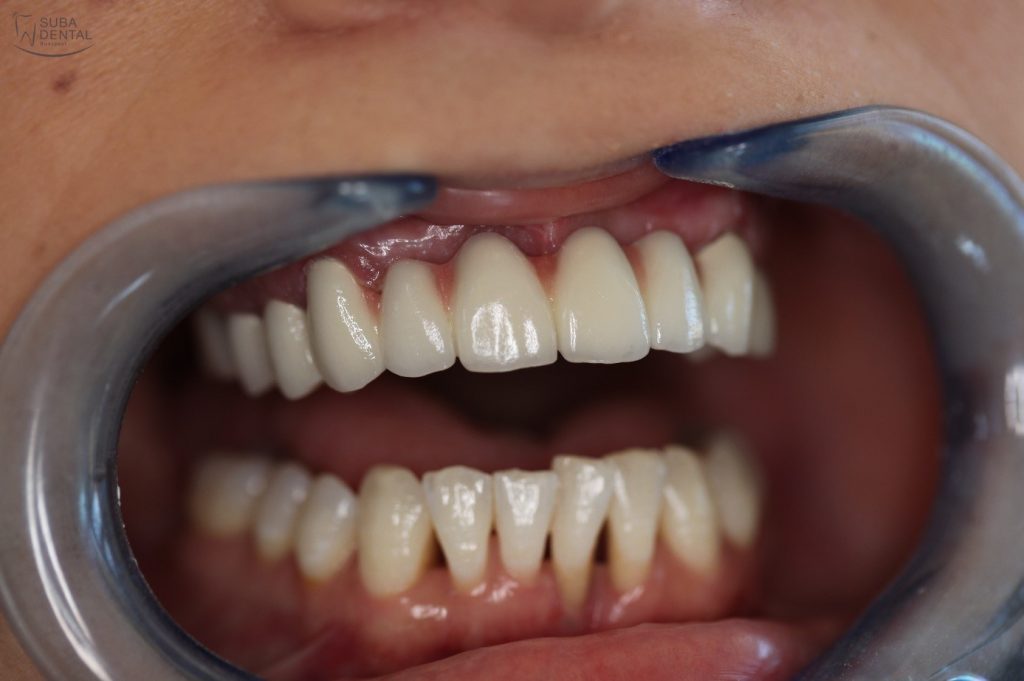

Az koronák végleges ragasztása után páciensünk újra boldogan tud mosolyogni, nem kell többé takargatnia a fogait.

A kész felső fémkerámia körhíd szájban